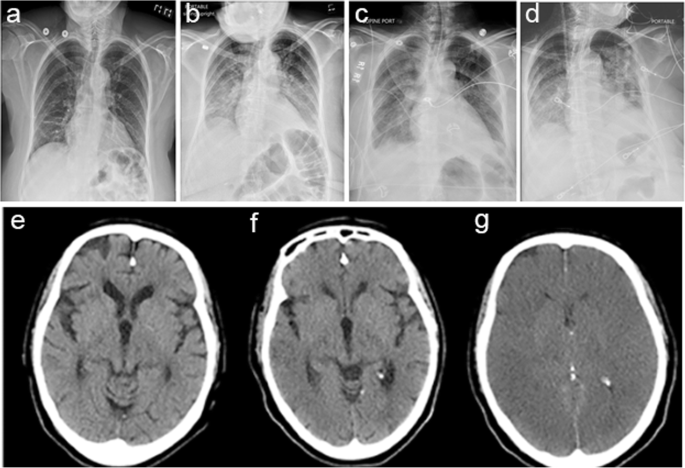

After this point, EEG suppression was persisted with rare (1–2 s) bursts of diffuse delta activity. Four subclinical nonconvulsive seizures (NCS) were observed over the right hemisphere lasting 30–75 s, and the last NCS was approximately 8 h after the GTCS. Portable chest X-ray showed possible aspiration pneumonia or mild neurogenic pulmonary edema (Fig. 2a to d). A repeat head CT scans 9 h after the GTCS did not show acute changes (Fig. 2e and f). After the GTCS, heart rate ranged between 70 and 100 bpm and O2Sat was > 96%. There was a significant fluctuation of systolic blood pressure between 50 and 180 mmHg with several bouts of hypotension < 60 mmHg (Fig. 3). Twelve hours later, the EEG became electrically silent and the patient developed dilated, unreactive pupils and absent brainstem reflexes, consistent with brain death. A repeat head CT showed diffuse cerebral edema and loss of gray-white differentiation (Fig. 2g). The patient subsequently died on the same day.

Periictal chest x-ray (CXR) and head CT (HCT) scan: a CXR on admission; b CXR 10 h prior to the terminal seizure; c CXR 4 h prior to the terminal seizure; d CXR 12 h after the terminal seizure: e HCT 11 h prior to the terminal seizure; f HCT 9 h after the terminal seizure without acute changes; g HCT 12 h after the terminal seizure with diffuse cerebral edema

There were likely two seizures prior to the likely terminal GTCS. One was un-witnessed, but suspected based on oxygen desaturation and urinary incontinence, and the other was witnessed by an EEG technologist prior to EEG being hooked up fully. Death occurred after the likely terminal GTCS when the patient was undergoing mechanical ventilation, presumably under the best case-scenario for SUDEP prevention after a seizure. However, the mechanical ventilation only delayed the death for 12 h. Meanwhile, PGES was observed after the GTCS in the presence of stable vital signs, including heart rate, blood pressure, body temperature and oxygen saturation at the time of seizure termination, suggesting the underlying pathogenesis of PGES might be related to seizure-induced diffuse cerebral suppression and is independent of cerebral oxygen saturation [12]. The causes of seizures were not clear. It was possible that CNS inflammation, infection and electrolyte disturbances might be contributory, but evidences supporting these causes were lacking. The cause of death in this case was likely due to diffuse cerebral edema and herniation as supported by the findings of head CT and autopsy results. Although the factors leading to diffuse cerebral edema were unclear, cerebral hypoxic injury related to seizure-induced autonomic dysfunction and hypotension (< 60 mmHg) might be the contributing factors (Fig. 3) [13]. Seizure induced central and peripheral apneas as commonly suspected mechanisms of SUDEP were unlikely the direct causes of death in this case, given that the patient was intubated and mechanically ventilated. There was no fatal cardiac arrhythmia based on the EKG recording. Consecutive chest X-ray did not show significant neurogenic pulmonary edema (Fig. 2).